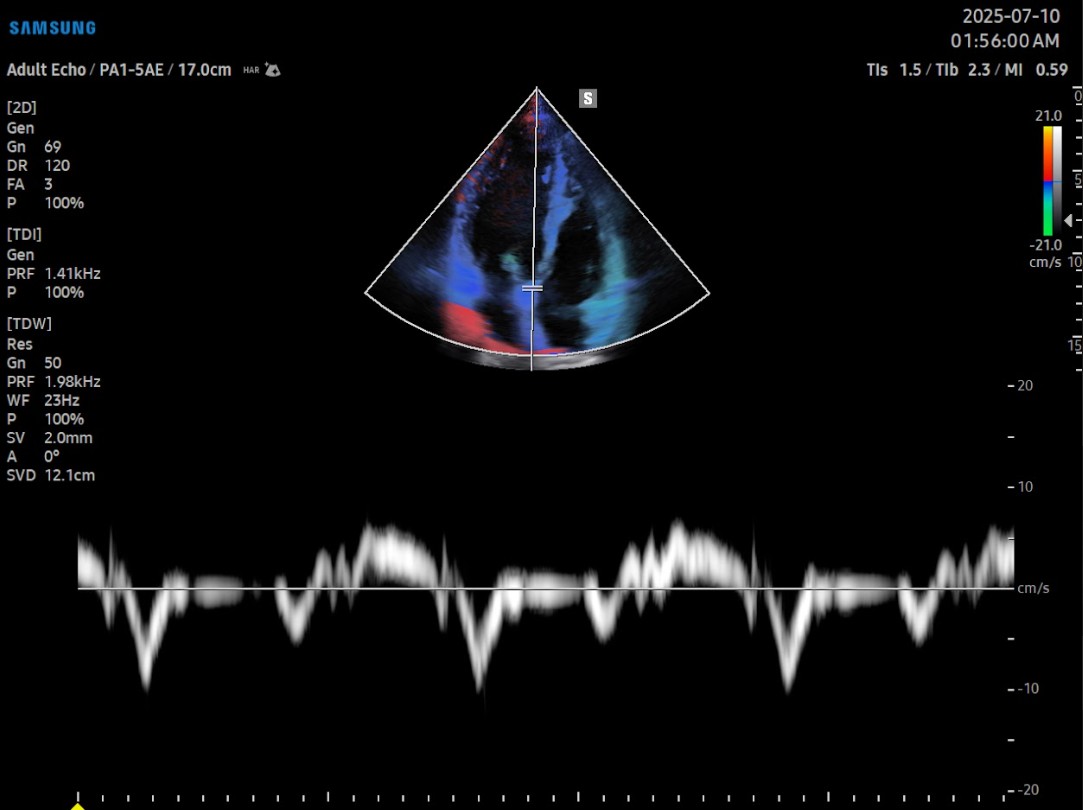

Gracias a su arquitectura Crystal™ (CrystalBeam™ y CrystalLive™), el cV6 entrega imágenes 2D y Doppler con gran claridad y resolución, lo que permite visualizar estructuras vasculares finas, flujos lentos y movimiento miocárdico con un nivel de detalle excepcional.Tecnologías como MV-Flow™, LumiFlow™, ClearVision y S-Flow™ optimizan la detección de microvasculatura y realzan el contraste sin sacrificar velocidad, siendo especialmente útiles en estudios cardiacos, vasculares y pediátricos.

En el ámbito cardiológico, el V6 incorpora herramientas avanzadas como HeartAssist™, que reconoce automáticamente las principales vistas cardíacas y facilita la orientación del operador. También incluye Strain+™, AutoEF™, StressEcho, y ArterialAnalysis™, que permiten evaluar la deformación ventricular, la fracción de eyección y la rigidez arterial de forma automatizada, estandarizando los resultados entre operadores y reduciendo los tiempos de exploración.